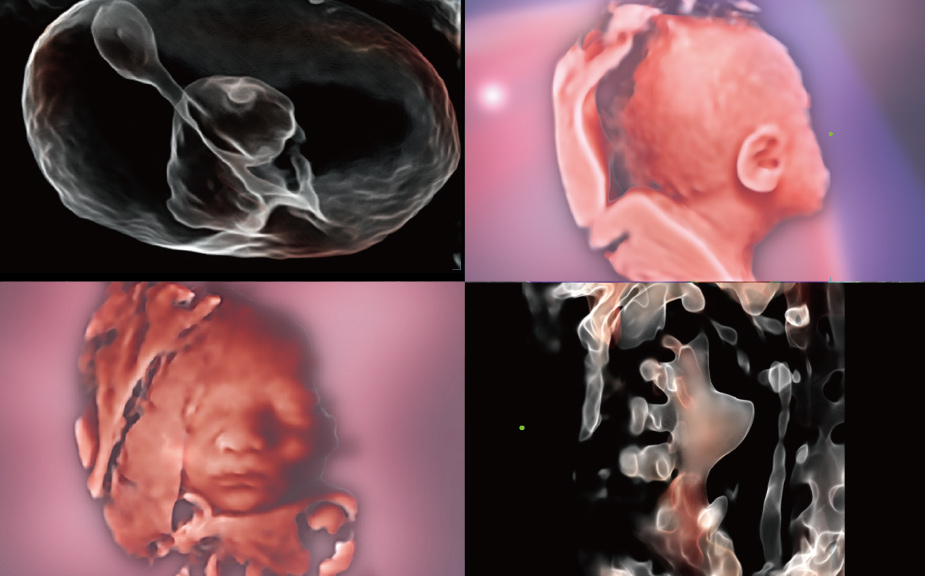

Con tecnologia ZST+

La piattaforma ZST+ rappresenta uno straordinario balzo in avanti nella tecnologia degli ultrasuoni, passando dal beamforming convenzionale all'elaborazione dei dati di canale. Questa innovazione rivoluzionaria supera i tradizionali compromessi tra risoluzione spaziale, risoluzione temporale e uniformit├Ā dei tessuti, dando vita a una qualit├Ā d'immagine senza pari che consente infinite soluzioni di imaging.

Intelligenza completa orientata allo scenario clinico

L'innovativa soluzione Smart Scene 3D consente l'identificazione automatica delle caratteristiche dei tessuti e fornisce una diagnosi specifica per i diversi distretti di esame durante l'intera procedura. Questa innovazione aumenta lŌĆÖaccuratezza e la sicurezza diagnostica, migliorando lŌĆÖefficienza.